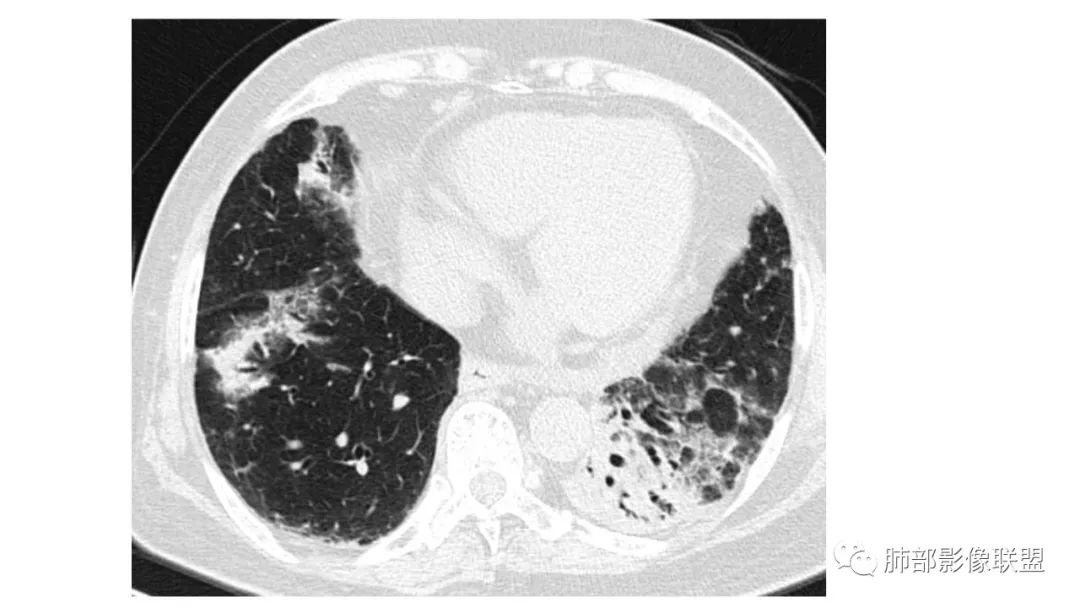

二、肺炎型

2、病灶常有一个主病灶,常位于下肺。后沿气道播散为多发病灶。

3、重力作用,叠瓦征。近叶间裂因重力效应,呈膨隆改变。

4、增强后不均匀强化,存在低强化区呈弱强化或无强化,因此可见“血管造影征。”血管毛糙与肺炎有统计学差异。

5、支气管粗细不均,呈“枯树枝征”,但与肺炎这一点鉴别不具有统计学差异。可发生支气管扩张

6、空腔形成,部分蜂窝状改变。

8、斑片常伴有结节,边缘清楚GGO或欠清楚。

4.回到本例,左下肺病变两次好转,均未经过肿瘤治疗,第一次是支气管镜后,第二次是当其他病变都在进展的情况下,左下肺病变范围反而缩小趋于浅淡。